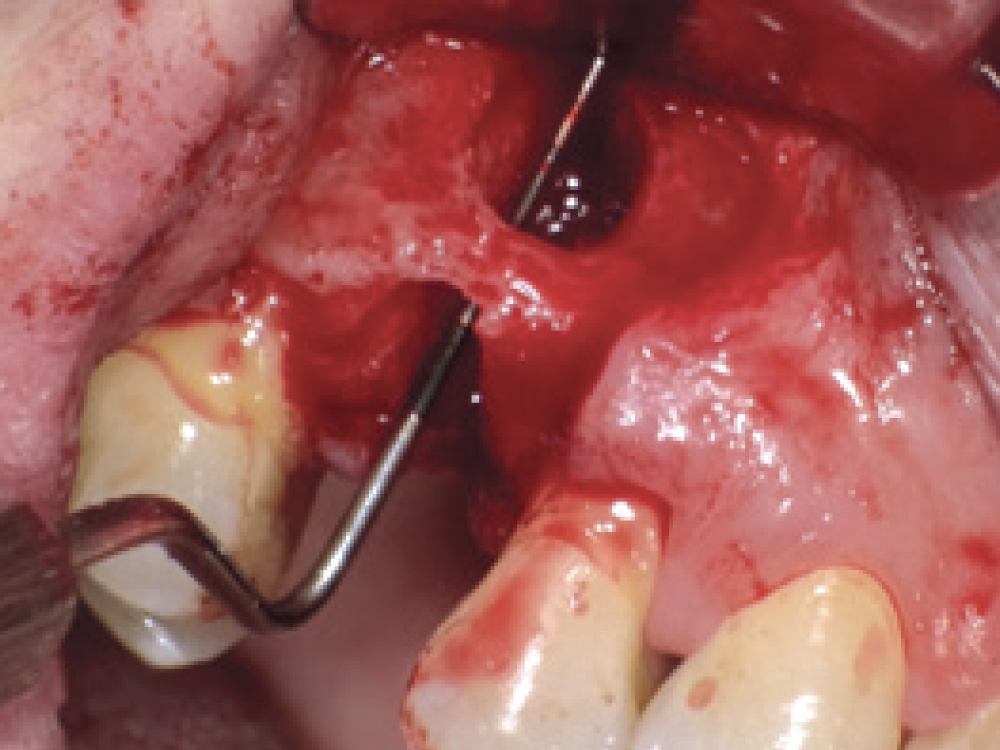

Bony Defect Evaluation A

Bony Defect Evaluation B

Bony Defect Evaluation C

Bony defect evaluation: (a) Flap reflection allows the clinician to visually evaluate the size and location of the fenestration to determine whether the defect will compromise implant positioning or primary stability when immediate implant placement is desired; (b) Examples of a large fenestration (green arrow) and loss of the buccal plate (blue arrow), either of which would contraindicate immediate implant placement due to the inability to obtain primary stability; (c) Additional example of flap reflection to show the fenestration.